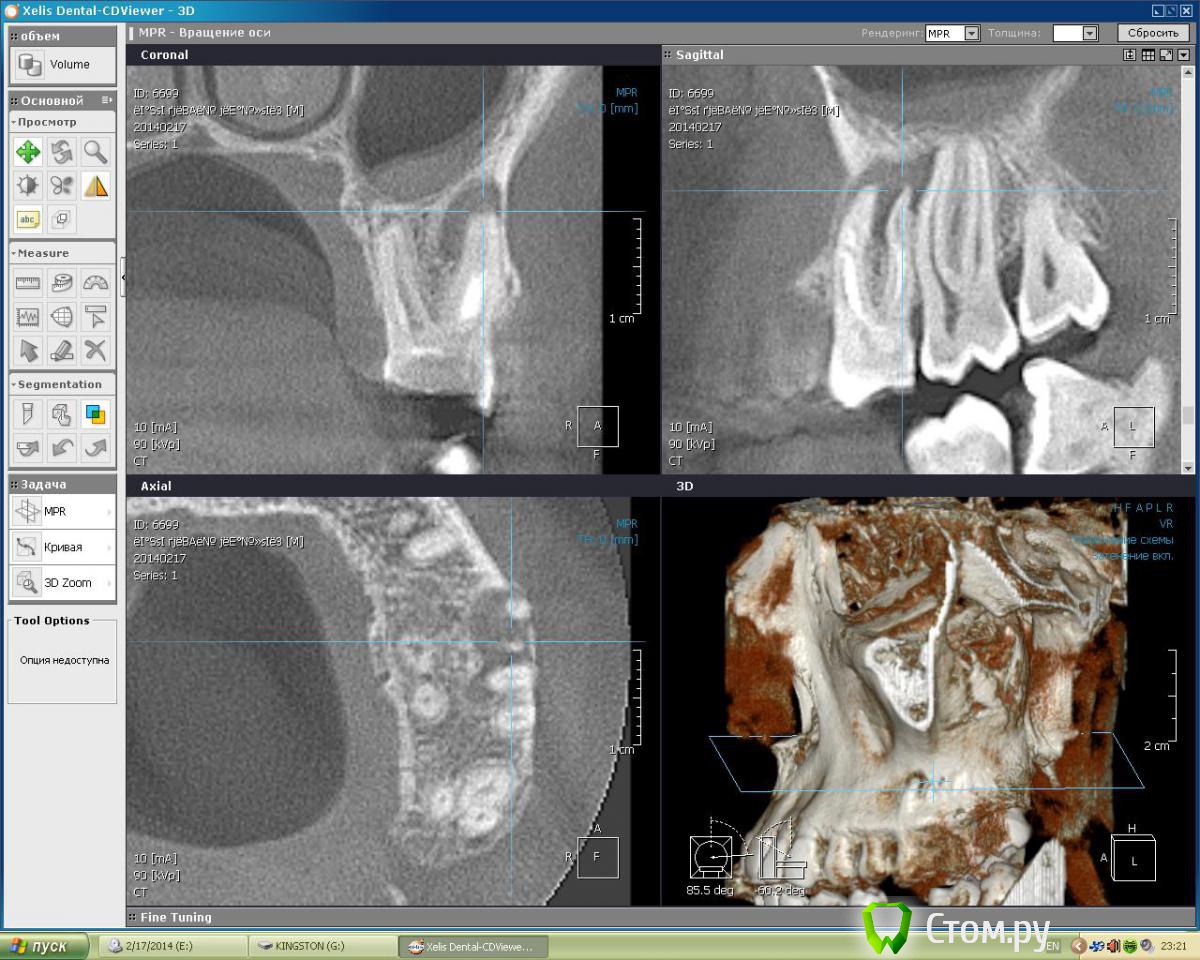

Dtm Опубликовано 1 марта, 2014 Автор Поделиться Опубликовано 1 марта, 2014 Подниму немного свою тему - сделал наконец то КТ, кажется я не ошибался в своих подозрениях на обе верхние 6-ки, что скажут уважаемые доктора? Ссылка на комментарий

Dtm Опубликовано 3 марта, 2014 Автор Поделиться Опубликовано 3 марта, 2014 Спасибо! На КТ видно что верхушки корней 6 контактируют с ВЧ пазухой - насколько велик риск при перепломбировании (я правильно понял?) вывести пломбировочный материал за верхушку корня в пазухи в данном случае? Ссылка на комментарий

Dtm Опубликовано 3 марта, 2014 Автор Поделиться Опубликовано 3 марта, 2014 Согласен, но для меня как пациента это имеет решающее значение - последствия могут быть неприятные. Может быть безопаснее удалить с имплантацией в перспективе? На левой 6 явно киста у корня? Насколько реально ее пролечить и как, просто сменить пломбу думаю не все, терапия какая то нужна в процессе, я имею ввиду вскрыть, ввести лекарство например? Ссылка на комментарий